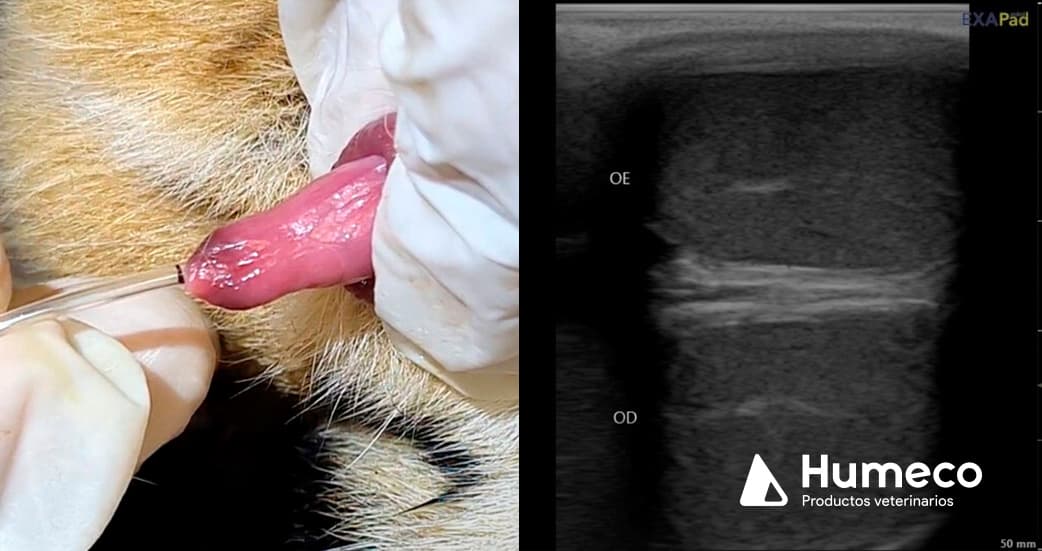

Este grupo de investigación tiene el objetivo de desarrollar biotecnologías reproductivas para la conservación de especies silvestres, y en este estudio ecografió los testículos de jaguares machos adultos usando el ecógrafo Exapad Mini, de IMV Imaging, y analizó las imágenes obtenidas usando el software Ecotext. Simultáneamente, se recolectó el semen a través de cateterismo uretral, y los espermatozoides fueron evaluados por CASA.

En el estudio preliminar se observa la misma pauta que la obtenida en otras especies: animales con mejor calidad seminal presentan una mayor densidad de áreas hipoecogénicas en la ecografía del parénquima testicular.

La rápida adopción de nuevas tecnologías reproductivas adaptadas para animales salvajes tiene un enorme potencial para ayudar en la conservación de las especies. Los parámetros de Ecotext se han asociado con la capacidad de producción de esperma y la calidad seminal en verracos, toros, carneros y caballos y camellos. La densidad y el diámetro promedio de las áreas hipoecogénicas, medidas por el software, también se correlacionan con anomalías morfológicas de los espermatozoides, de modo que los animales con puntuaciones Ecotext más altas tienen menos espermatozoides con formas aberrantes.